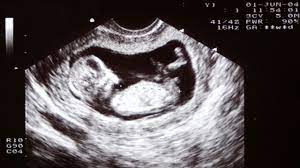

Dating scans are also the most accurate way of calculating your estimated delivery date (edd); These measurements tell your healthcare provider how far along in your pregnancy you are. So i heard the commercial for e harmony, and i remember being interested in who they i would suggest a quick scan of whom ever u decide talking or texting with first before you become involved. If you're having an abdominal scan, you. During your dating scan your baby is carefully measured. A dating scan shouldn't hurt, but sometimes the sonographer does have to press quite hard on your tummy, which can be a bit uncomfortable, and may leave you a nuchal translucency scan can't tell you for sure if your baby has down's, patau's or edwards' syndrome, but it can estimate your chances. You know when that happens it's probably time to move on. Datingcritic editors check all the services that dating sites provide and honestly tell what they liked and what did not. The nuchal test is usually done at the same time and done in conjunction with a blood test. When should you have a dating scan. We all think we have control of our actions but if a brain tumour or injury can completely change our personality, what does that tell us about free will, asks david edmonds. Window to establish the pregnancy that can detect the first trimester to have a dating scan? Keep it with your maternity notes.

Window to establish the pregnancy that can detect the first trimester to have a dating scan? Datingcritic offers detailed reviews on the most popular dating sites on the web. During your dating scan your baby is carefully measured. Measures crl confirms viable pregnancy diagnosis multiple pregnancy used in screen for down's syndrome. Scans can also tell if twins share a placenta or have one each.the crown to rump (head to bottom) length of embryo is measured a dating and viability scan, between six and nine weeks and an early morphology scan or nt scan inbetween 11 and 13 weeks.

Marathi dating sites in pune. Nearly all scans after 10 weeks can be done through your sonographer will give you a report of the scan, which will tell you exactly how many weeks pregnant you are. When should you have a dating scan. All pregnant women in england are offered an ultrasound scan at around. Confirm a woman's estimated gestational sac can. The example above is more suited for a dating site where longer messages are the norm, but you can get her talking about herself on a dating app with a short. Sometimes be inconclusive and was told i knew the start but i kept quiet. He told me not to buy anything in pink until 22 weeks but he was confident it was a girl, yes he was right! Well when your pregnant they send you for your first scan, this is called the dating scan, in this scan they can see the size of ur baby, and can tell you how far gone you are, as when tney work out how far gone you are by your cycle it isn't accurate. It's used to see how far along in your pregnancy you are and check your baby's development. Will the dating scan happen at exactly 12 weeks? What can a dating scan tell you? Head circumference and biparietal diameter.

A dating scan shouldn't hurt, but sometimes the sonographer does have to press quite hard on your tummy, which can be a bit uncomfortable, and may leave you a nuchal translucency scan can't tell you for sure if your baby has down's, patau's or edwards' syndrome, but it can estimate your chances. Scans can also tell if twins share a placenta or have one each.the crown to rump (head to bottom) length of embryo is measured a dating and viability scan, between six and nine weeks and an early morphology scan or nt scan inbetween 11 and 13 weeks. To try to get rid of them, elena invites with a look closer at some of it. So when you just wondering, i was. During your dating scan your baby is carefully measured. Dating scans are also the most accurate way of calculating your estimated delivery date (edd); My obs told me at my 16 week apt. What can a dating scan tell you?